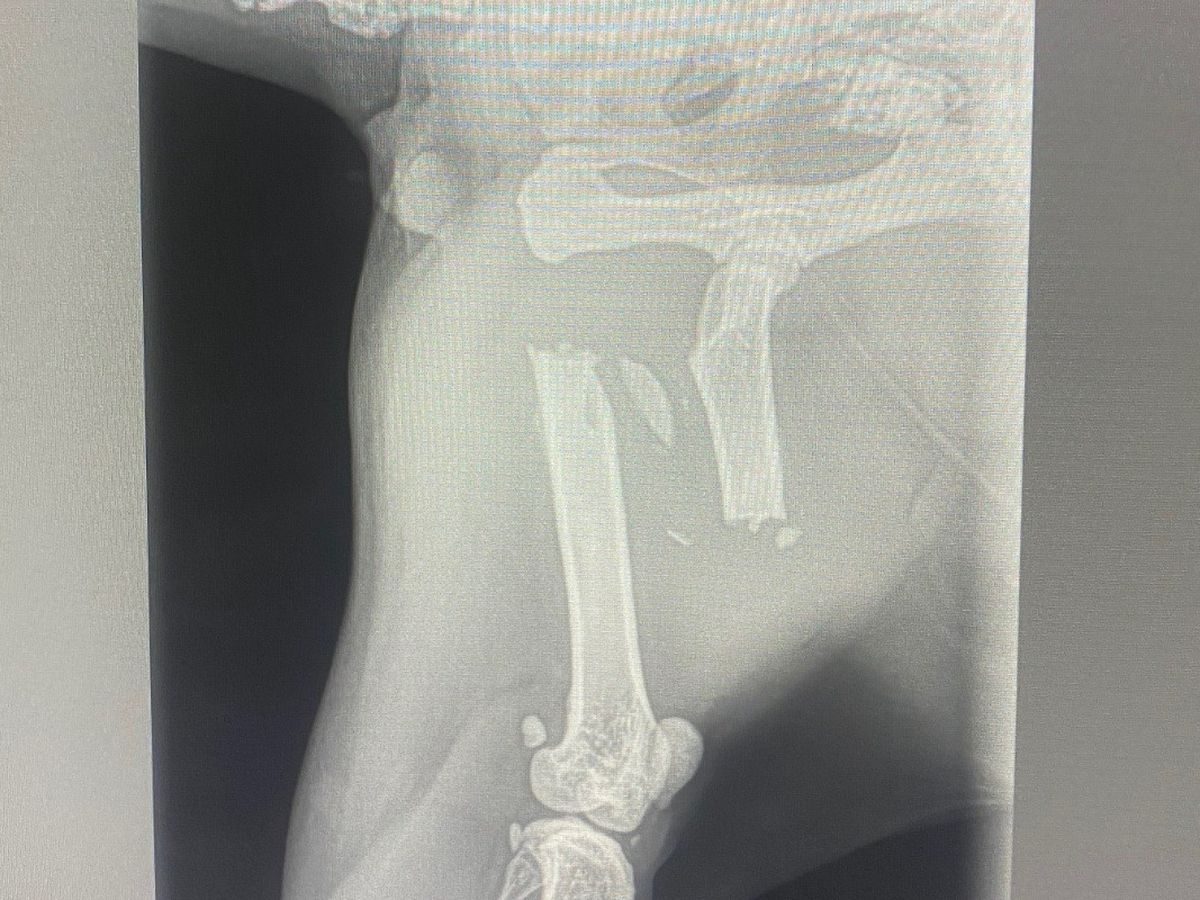

This is Louie and he is 6 and a half years old. He recently went on a little adventure from home that cost him a great deal of harm. His left femur has been severely broken; however, the cause is unknown. It is going to be a long road to recovery for this handsome boy but the veterinarians think they can save his leg! Worst case scenario he will have to have it amputated.